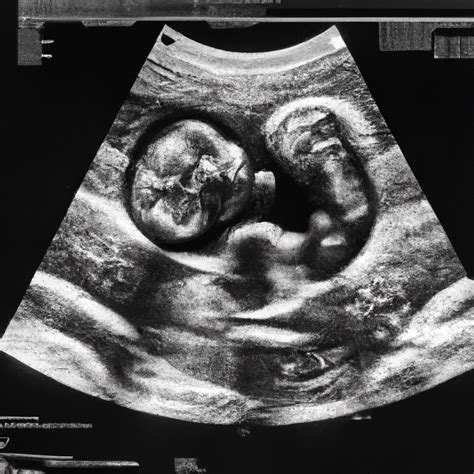

• Ultrasound: Uses sound waves to create images and is generally considered safe during pregnancy.

After a CT scan while pregnant, it is essential to monitor the pregnancy closely. Regular prenatal check-ups and ultrasounds can help ensure the health and development of the fetus. If there are any concerns or unusual symptoms, it is crucial to inform the healthcare provider immediately.